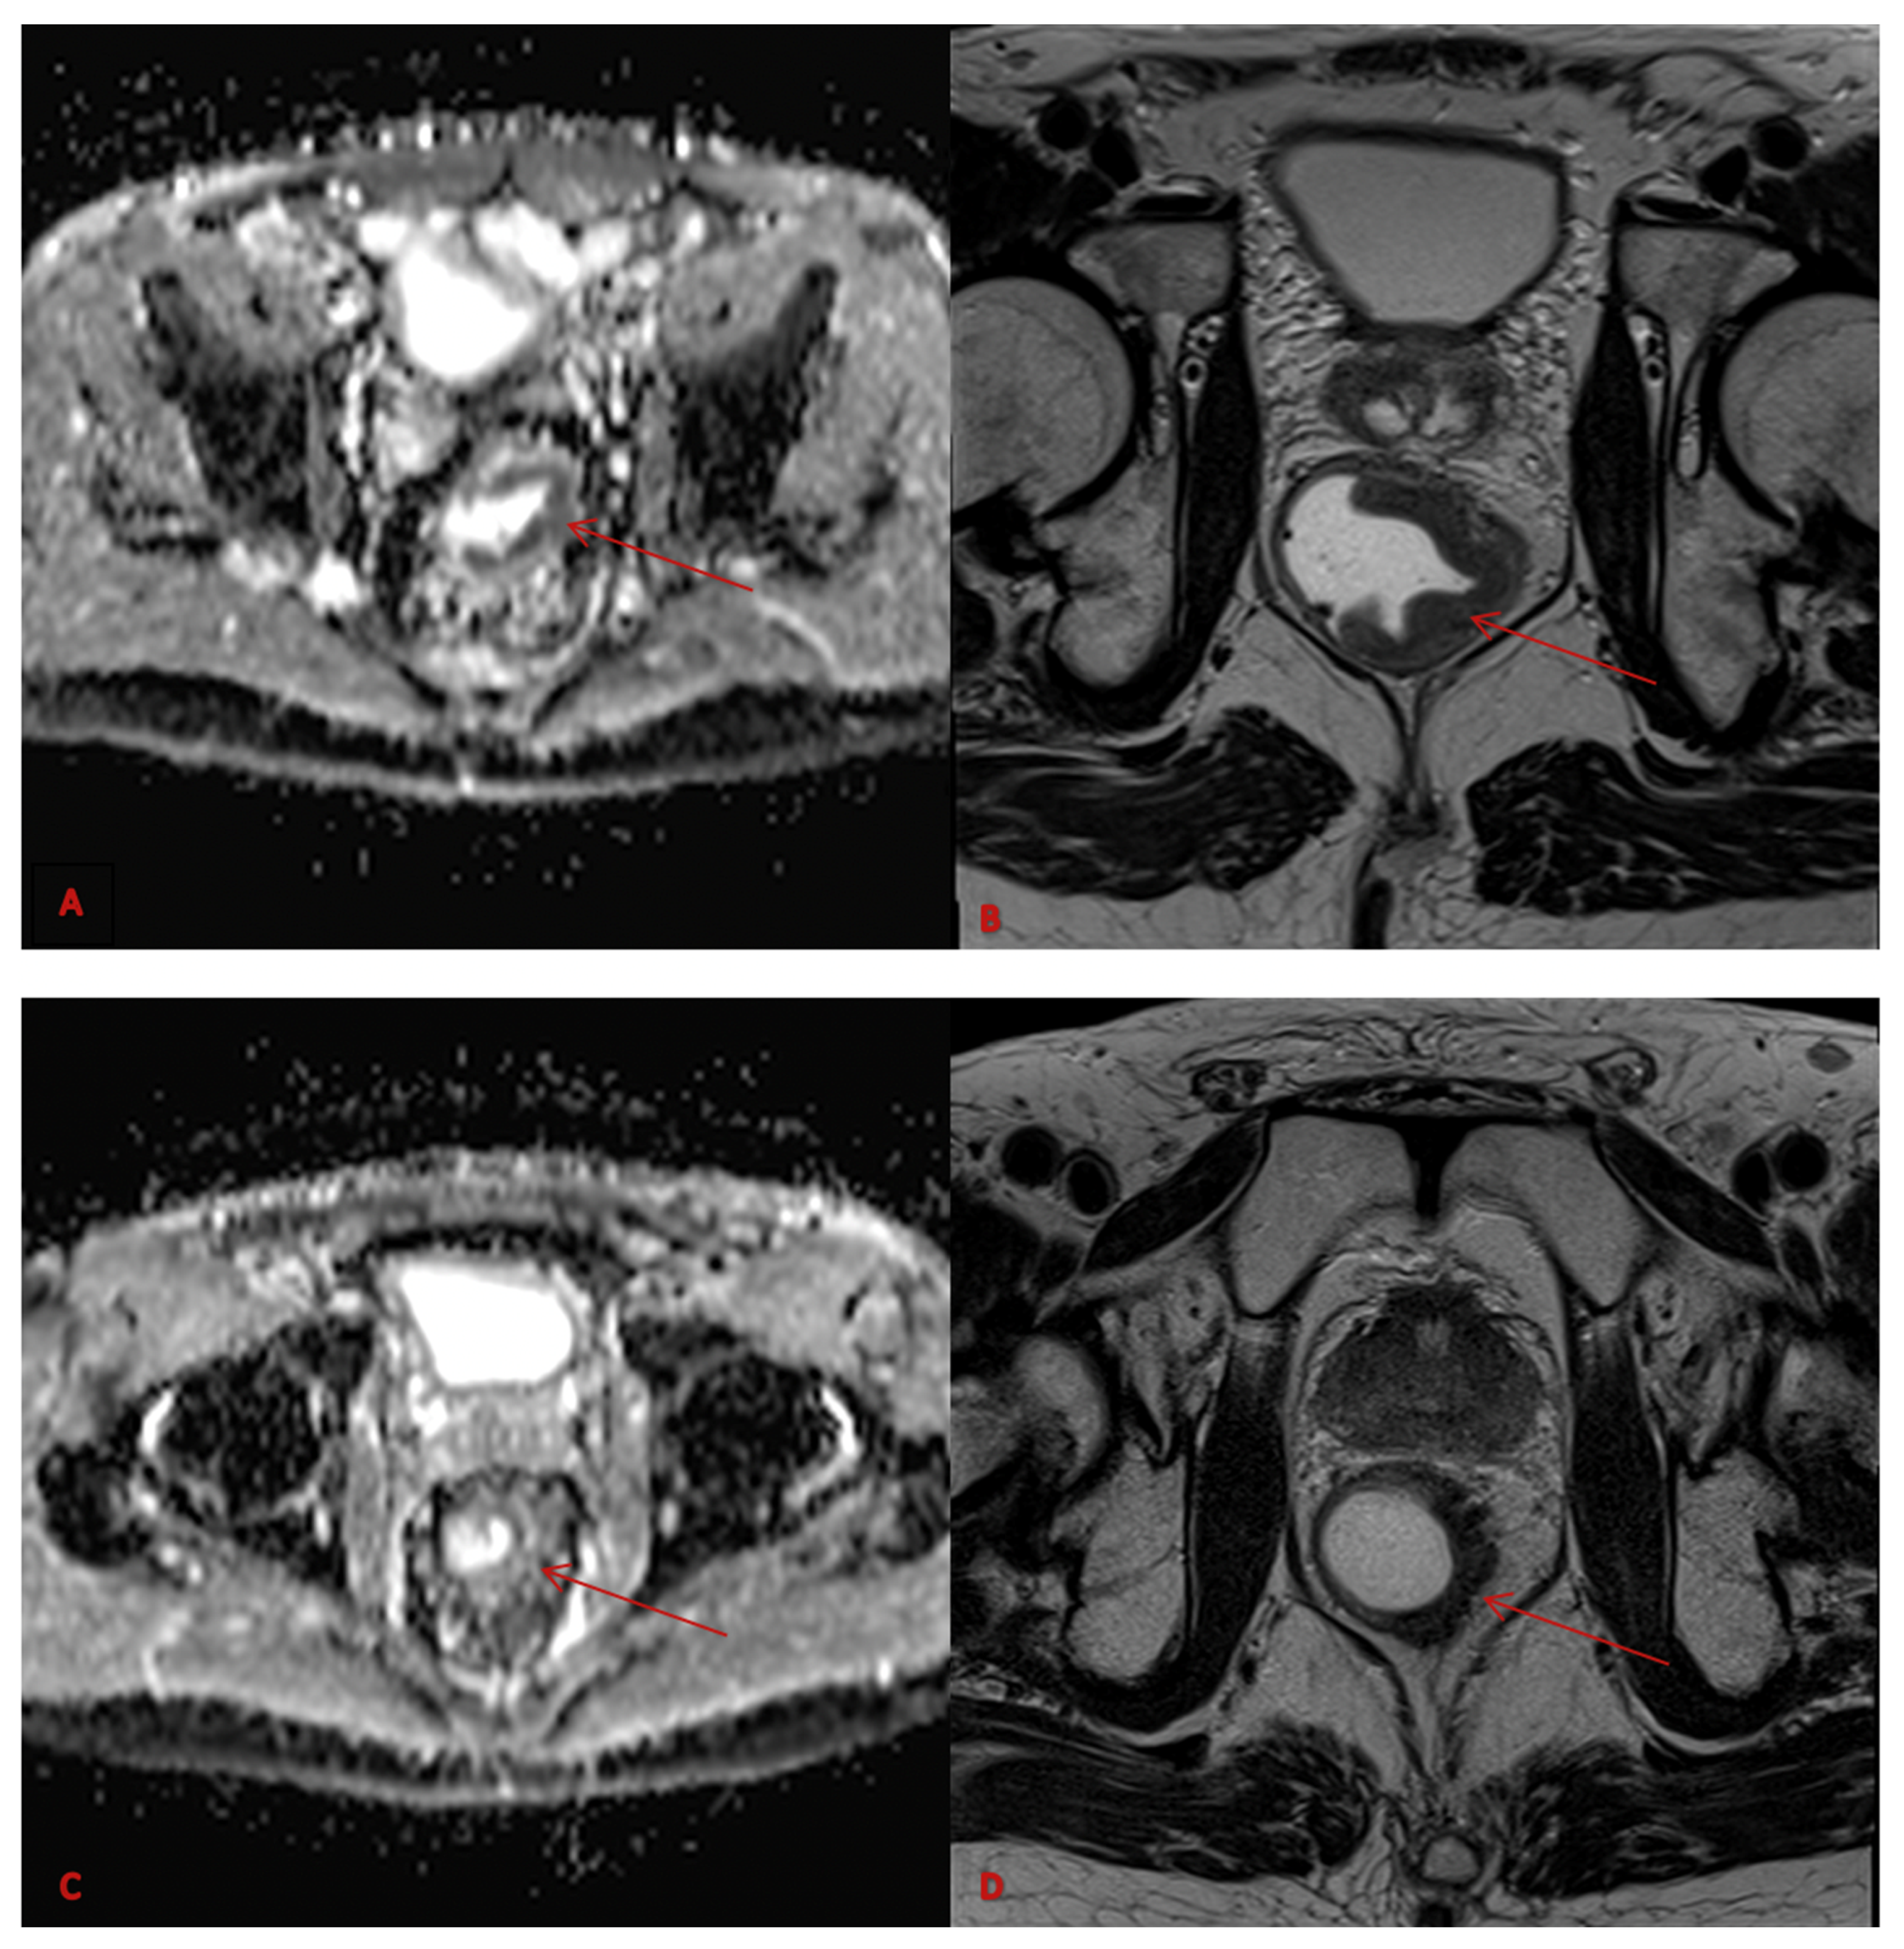

2.4. Imaging Analysis

2.5. Radiomic Workflow